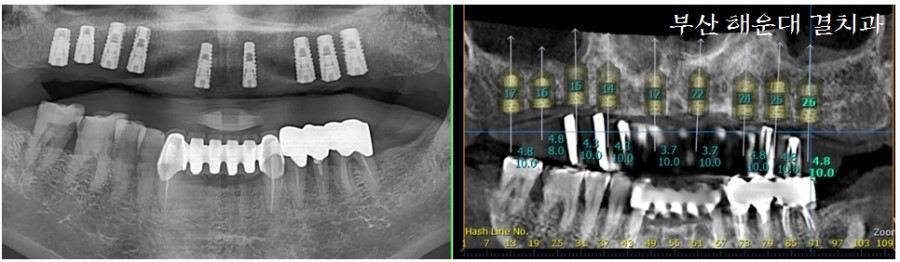

발치 후 임플란트 식립 사진입니다. 역학적으로 꼭 필요한 부위에만 임플란트를 식립하고, 사이에 비어있는 공간은 '브릿지 보철'로 수복 할 수 있도록 게획하였습니다.

식립 후 사진(좌)과 CT분석(우)에서의 사진을 비교해 보면 거의 동일한 위치에 임플란트가 정확히 식립되어 있는것을 볼 수 있습니다. 해운대 결치과는 대학병원에서 임플란트 수술을 전문으로 많은 수술경험을 갖고 있기 때문에 안심하고 수술을 받으시면 됩니다!